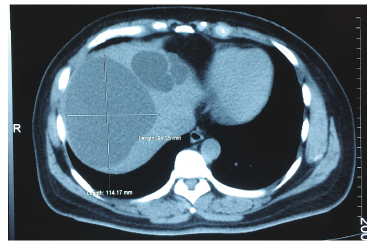

Se realizó una tomografía de abdomen que informó hígado de tamaño normal, contornos regulares, con imágenes hipodensas de contornos bien definidos con densidad de agua (8 UH), dispersas en el lóbulo derecho e izquierdo; la de mayor tamaño mide 114 x 94 x 105 mm en el segmento hepático VIII y otras de menor tamaño que miden entre 10 y 20 mm en el segmento II y VII; no hay dilatación de las vías biliares, ni lesiones de aspecto metastásico, colecistectomía. (Figura 3).